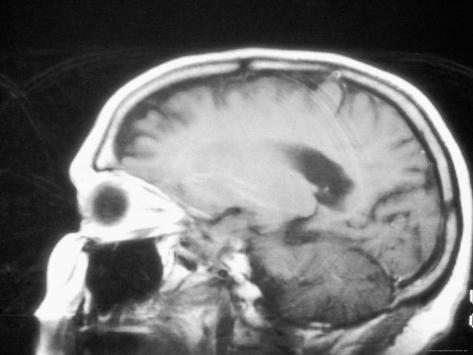

Investigations Modern imaging studies can now localise lesions with great accuracy. MRI tends to be better than CT. If metastatic cancer is suspected, a CXR is required. ... Retrieve Content